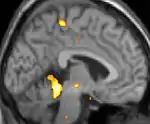

Neuro-imagerie

La tomographie par émission de positons (TEP) montre les zones du cerveau étant activées durant la douleur

La morphométrie voxel par voxel (VBM) montre les différences structurelles des zones du cerveau

Les images par tomographie à émission de positron indiquent les régions du cerveau qui sont activées lors de la douleur, par rapport aux périodes sans douleur. Elles montrent les régions du cerveau qui sont toujours actives durant la douleur en jaune/orange (appelé "matrice-douleur"). La zone au centre (dans les trois vues) est spécifiquement activée uniquement pendant la crise. Les photos sur la ligne du bas (effectuées par VBM) montrent les différences structurelles entre les patients souffrant d'AVF et des personnes saines : seulement une partie de l'hypothalamus est différente[50],[51].

Il semble exister des anomalies microstructurales hypothalamiques bilatérales (en l'occurrence l'existence d'une hypertrophie)[52] sans que l'on sache si ces anomalies sont la cause ou la conséquence de la répétition des crises.